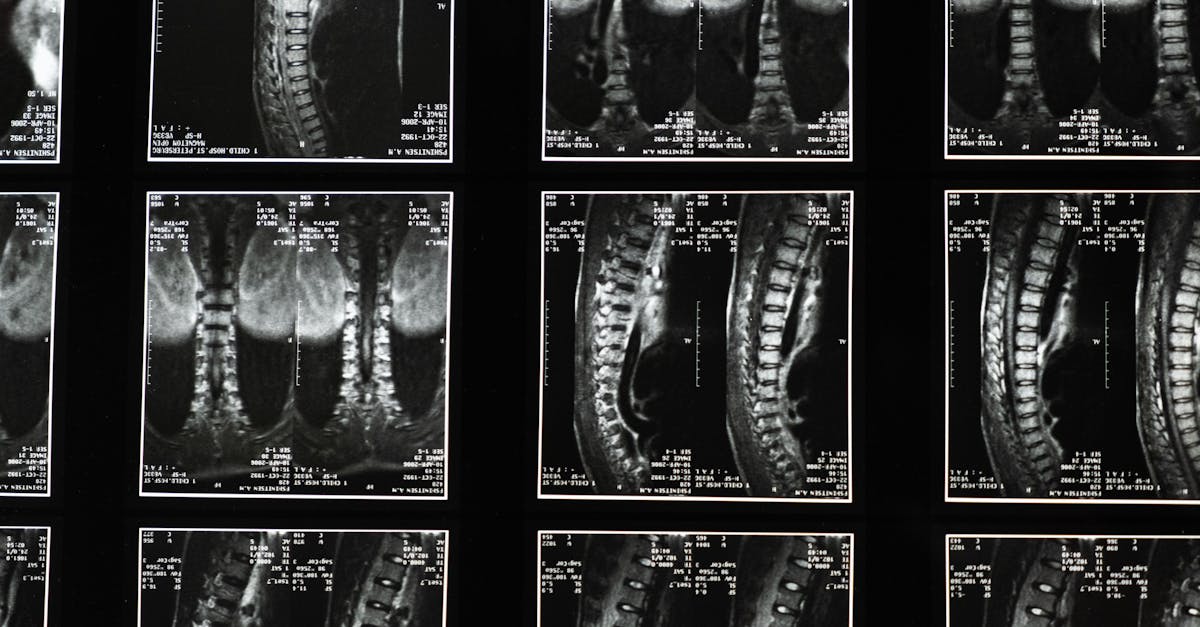

Are you struggling with chronic pain due to a herniated disc, bulging disc, or conditions like spinal stenosis? TAGMED offers an advanced Spinal Decompression Therapy that provides a non-surgical solution specifically designed to address moderate-to-severe disc issues. By gently reducing pressure on the affected discs and nerves, this specialized technique helps enhance mobility, alleviate pain, and support your bodyβs natural healing process. If youβve reached a plateau with other therapies, discover how TAGMEDβs evidence-based decompression approach can help you resume an active, comfortable life.

TAGMEDβs neurovertebral decompression applies a controlled, progressive traction force to the spine, effectively increasing the space between vertebrae. This method reduces pressure on intervertebral discs and nerve roots, promoting better fluid circulation in the targeted area. As a result, inflammation is lowered, leading to pain relief and offering a reliable, non-invasive solution for individuals suffering from chronic back pain.

This non-invasive approach effectively alleviates chronic pain and symptoms linked to conditions like disc herniation and foraminal stenosis. By optimizing fluid circulation around the discs, TAGMEDβs therapy supports recovery and enhances the quality of life for a variety of patients seeking relief from persistent discomfort. Patients have reported significant benefits, including mobility enhancement and heightened comfort levels.